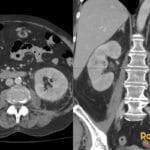

- Radiology Cases: Images with a to-the-point discussion highlighting the specific diagnostic criteria.

- Radiology Case of the Day Collection: Aunt-Minnie Board Cases for Rapid Review.

- Radiology Spotters: 700+ spot / “Aunt-Minnie” cases divided into sets of 10 each!